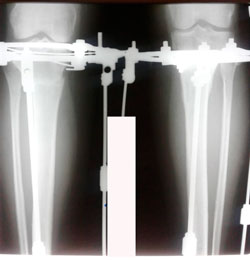

Перед крутками

Вложения

image-23-03-20-12-24.jpg